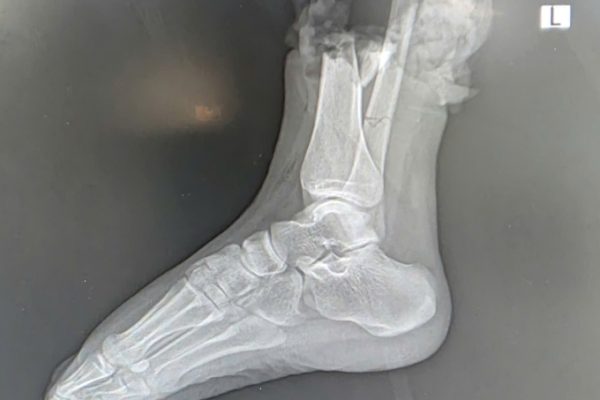

Nối thành công bàn chân đứt lìa cho nữ sinh 19 tuổi

Các bác sĩ Bệnh viện 108 cho biết, sức khỏe của nữ sinh bị tai nạn giao thông nghiêm trọng trên phố Trịnh Văn Bô đã có những chuyển biến tích cực sau hai tuần điều trị. Bệnh nhân đã có thể cử động các ngón chân, cho thấy dấu hiệu phục hồi tốt. Vụ…